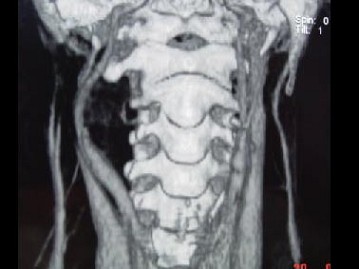

男,41岁,右侧咽部不适两年余,有异物感,声音嘶哑,CT如图所示,最可能诊断为 ( ) EBH-00941.jpg EBH-00942.jpg EBH-00943.jpg EBH-00944.jpg

题型: 单选题 分类: 耳鼻喉(头颈外科)学

• A.咽旁转移癌

• B.咽旁神经鞘膜瘤

• C.颈动脉体瘤

• D.咽旁淋巴瘤

• E.小唾液腺瘤